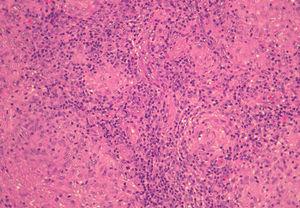

Se realizó una biopsia de la lesión facial y del borde activo de la placa del antebrazo. El estudio histológico mostró, bajo una epidermis respetada, un infiltrado granulomatoso dérmico (fig. 3). Los granulomas eran de tipo tuberculoide, aunque sin necrosis caseosa central. Estos granulomas eran confluentes, formados por histiocitos, algunos de aspecto espumoso y escasas células de Langhans. En la periferia de los granulomas se observaban abundantes linfocitos (fig. 4). En la tinción con de Ziehl-Neelsen no se detectaron bacilos ácido-alcohol resistentes.

Fig. 4.--Detalle de los granulomas tuberculoides formados por histiocitos y con abundantes linfocitos en la periferia. (Hematoxilina-eosina, x20.)